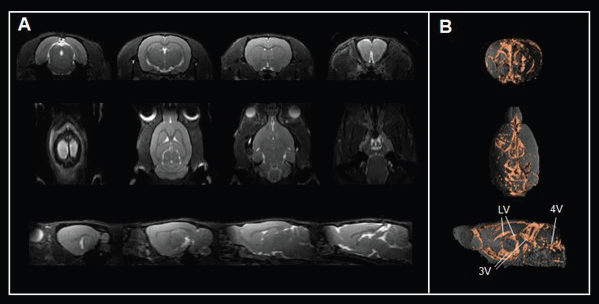

For instance, true fast imaging with steady-state precession (TrueFISP) sequence contrasts cerebrospinal fluid spaces (Fig. 5A) and 3D renderings (Fig. 5B), allowing the assessment of ventricle anatomy and morphology, a critical area for cerebrospinal fluid production and transport.

Assessing brain ventricles. A) Axial, coronal, and sagittal T2-weighted TrueFISP images and B) corresponding renderings reveal the cerebrospinal fluid spaces in the rat brain. Rat brain data was acquired with a BioSpec Maxwell 94/17 using a volume coil for transmission and a phased-array coil for reception. Tissues were segmented and rendered using PMOD. LV = lateral ventricle; 3V = third ventricle; 4V = forth ventricle

Figure 5. Assessing brain ventricles. A) Axial, coronal, and sagittal T2-weighted TrueFISP images and B) corresponding renderings reveal the cerebrospinal fluid spaces in the rat brain. Rat brain data was acquired with a BioSpec Maxwell 94/17 using a volume coil for transmission and a phased-array coil for reception. Tissues were segmented and rendered using PMOD. LV = lateral ventricle; 3V = third ventricle; 4V = forth ventricle. Image Credit: Bruker BioSpin Group